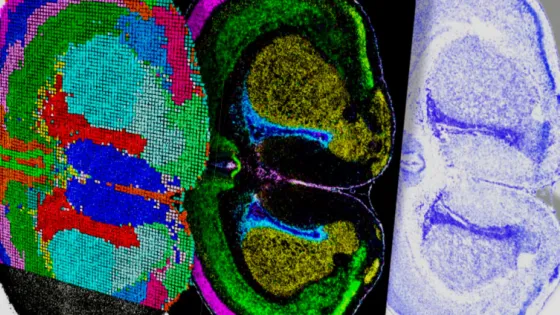

Обложка: Изображение из статьи. Мультиомное картирование мозга мыши после рождения Di Zhang / Yale University / Nature